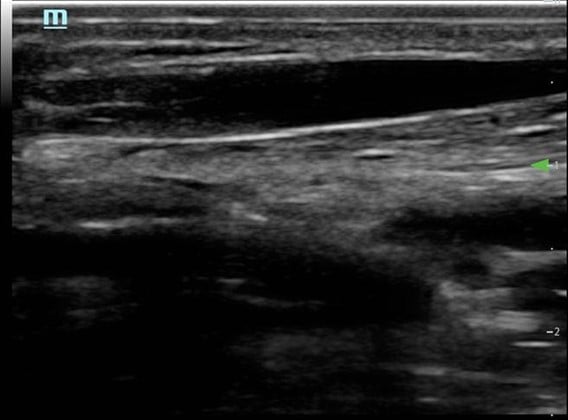

- Needle and vessel kept in the same plane (Fig. 6)

Figure 6. Long axis approach: Vessel appearance